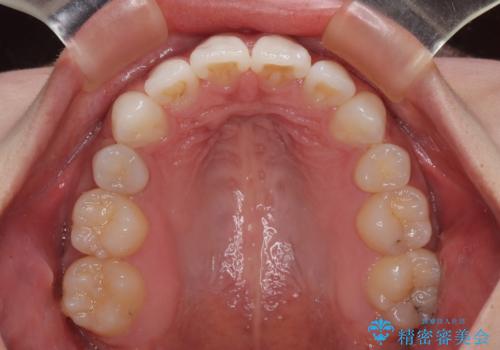

左右ともに奥歯の咬み合わせに問題があり、上顎臼歯が前方位にある状態で、結果として上顎前歯全体が前方位かつ叢生になっていました。

補助装置を用いて上顎歯列全体を後方に移動させ、下顎は左右で抜歯する小臼歯を変えることで、左右の咬み合わせをより理想的な位置となるように計画しました。